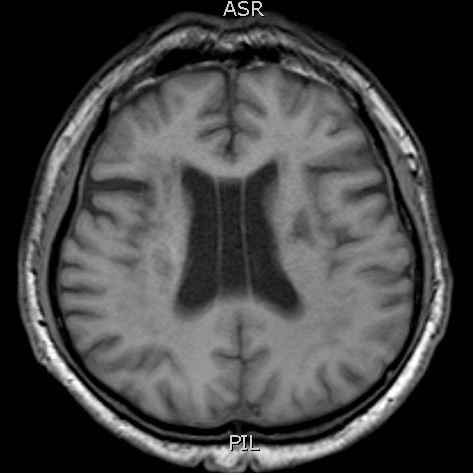

T1